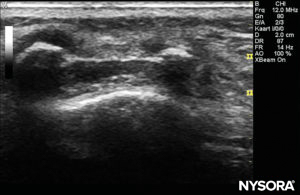

The probe is positioned first in a transverse plane at the sacrum level; this is called the short-axis view (SAX). The exact position of the cornua and the sacrococcygeal membrane (SCM) are defined (Figure 4). With the sacrococcygeal membrane in the middle of the image (Figure 5), the probe is then rotated 90 degrees into a midline sagittal position over the lower sacrum, which is called the long-axis view (LAX; Figure 6). The SCM and the ventral and dorsal layer of the os sacrum, with the caudal epidural space in between, are easily identified. In small children, the dural sac may be visible in this position, although in older children you need to scan more in a more cephalad direction (Figure 7). These movements can be performed in the opposite order, but a complete exploration of the space in both axes is recommended.

FIGURE 5. US image in the short-axis view showing the sacral cornea and sacrococcygeal membrane.